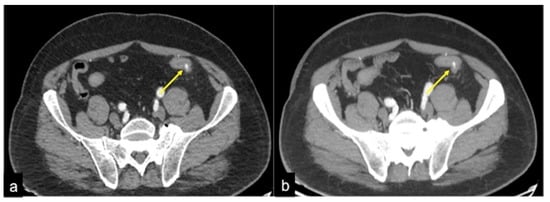

| Diverticulosis (Figure 33) | Asymptomatic or bleeding. | Protruding sacs where the vessels pass through the muscularis layer, between the mesenteric and antimesenteric taenia. |